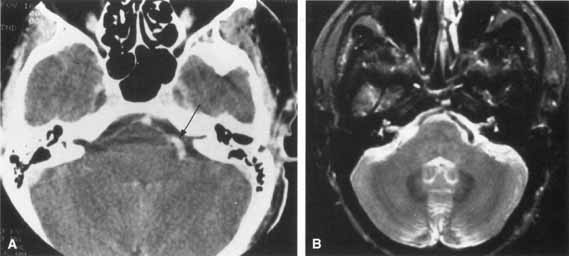

On CT scan, acoustic neuromas may be seen as enhancing masses in the internal auditory canal or cerebellopontine angle. For smaller tumors, gadolinium-enhanced MRI may be very helpful. On T1-weighted gadolinium images, neuromas may appear as uniformly enhancing masses, effacing the brain stem and cerebellum with extension into the internal auditory meatus or canal. On T2-weighted images these lesions appear hyperintense (Fig. 15).89 Treatment usually consists of microsurgical excision with the use of techniques that may provide complete removal of tumor and preservation of the facial nerve. Intraoperative facial nerve monitoring during acoustic neuroma surgery may improve the preservation of facial nerve function.90,91 Spontaneous recovery of facial function usually begins by 3 to 4 months after surgery and is typically finished by 1 year. Those palsies persisting beyond one year are likely to be permanent.92

Fig. 15 Magnetic resonance imaging of acoustic neuroma. A. Coronal section through pons showing bilateral acoustic neuromas in a patient with neurofibromatosis. B. Normal study of same area.